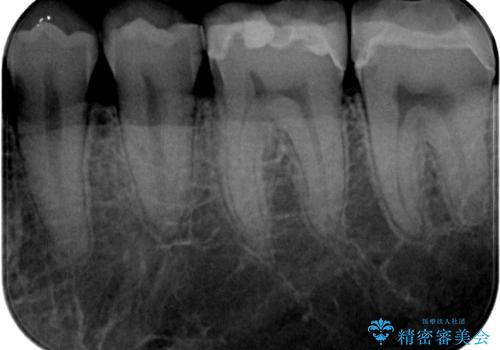

銀歯を白くしたい セラミックインレー修復

- 当院に矯正治療で通院されており矯正治療後に銀歯が目立つので白くしたいとのことでした。

拡大鏡視野下でメタルインレー、虫歯の除去を行い、セラミックインレーに適した形に整えました。

歯と歯茎の間に圧排糸と言われる糸を入れてシリコーン印象材にて精密な型どりをしました。

セラミックインレーの装着時には、唾液の侵入を防ぐために、ラバーダム防湿を行いました。